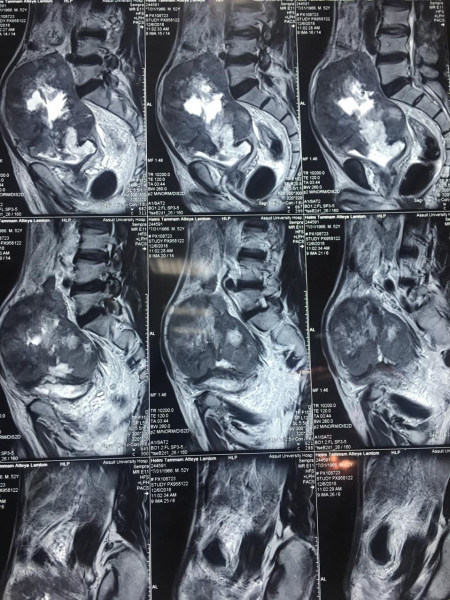

أعلن الدكتور هشام مختار حمودة رئيس قسم جراحة المسالك البولية والكلى بجامعة أسيوط ومدير مستشفى المسالك البولية والكلى الجامعي بأسيوط عن نجاح فريق طبي بالقسم في استئصال ورم سرطاني بالمثانة البولية والذي بلغ حجمه 15سم ووزنه 7كجم.